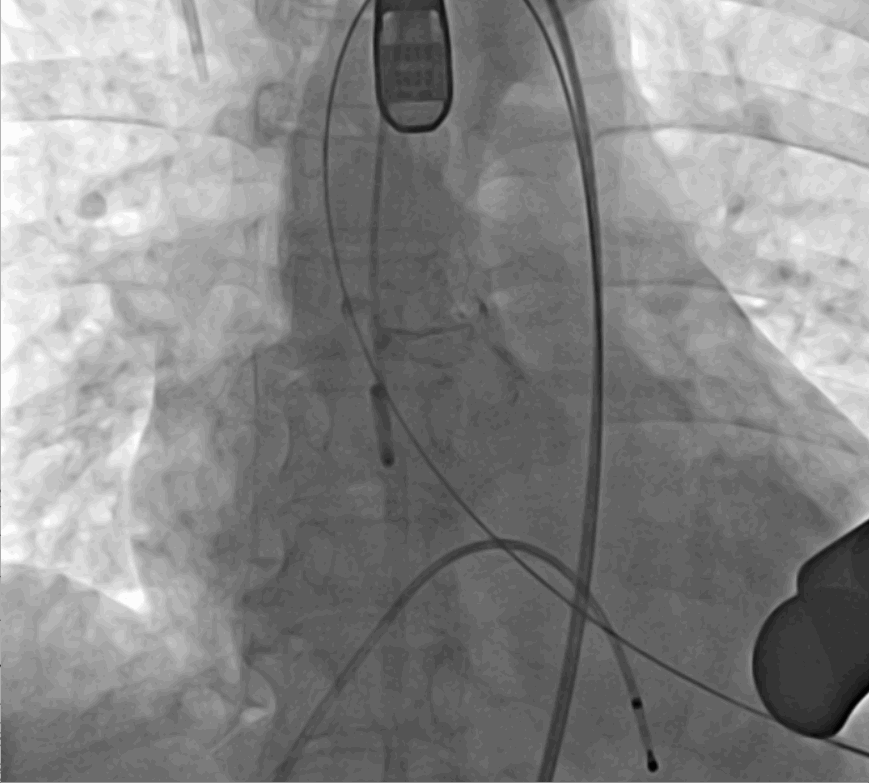

手術(shù)采用經(jīng)心尖入路,對(duì)患者進(jìn)行全麻后,在左側(cè)心尖處做3-4cm微創(chuàng)手術(shù)切口,在DSA及超聲引導(dǎo)下手術(shù)順利完成。從導(dǎo)入器械到完成瓣膜置入,僅耗時(shí)約10分鐘。術(shù)后即刻主動(dòng)脈瓣返流程度由術(shù)前大量返流轉(zhuǎn)為消失,患者于導(dǎo)管室拔除氣管插管,次日由ICU轉(zhuǎn)入普通病房。

術(shù)前DSA影像圖

術(shù)中釋放定位鍵后DSA影像圖